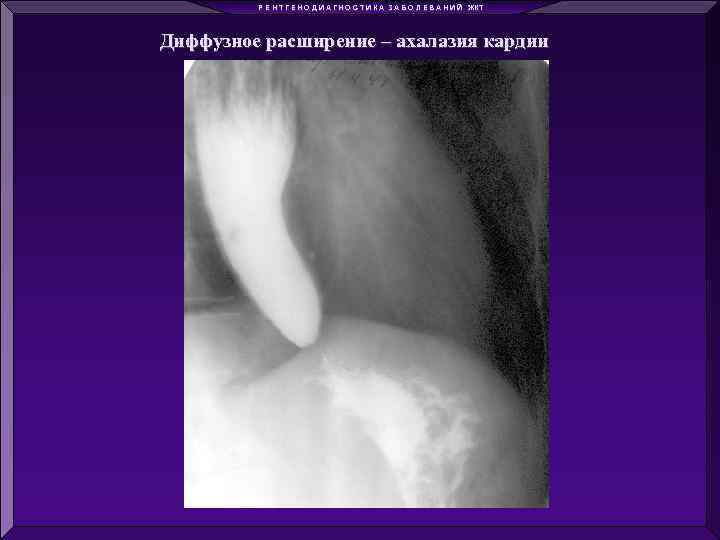

Р Е Н Т Г Е Н О Д И А Г Н О С Т И К А З А Б О Л Е В А Н И Й ЖКТ Диффузное сужение - ожог Локальное сужение - опухоль Диффузное расширение – ахалазия кардии Локальное расширение - дивертикулы

Р Е Н Т Г Е Н О Д И А Г Н О С Т И К А З А Б О Л Е В А Н И Й ЖКТ Диффузное сужение - ожог Локальное сужение - опухоль Диффузное расширение – ахалазия кардии Локальное расширение - дивертикулы

Р Е Н Т Г Е Н О Д И А Г Н О С Т И К А З А Б О Л Е В А Н И Й ЖКТ Диффузное расширение – ахалазия кардии Обзорная рентгенограмма Контрастирование Ва

Р Е Н Т Г Е Н О Д И А Г Н О С Т И К А З А Б О Л Е В А Н И Й ЖКТ Диффузное расширение – ахалазия кардии Обзорная рентгенограмма Контрастирование Ва

Р Е Н Т Г Е Н О Д И А Г Н О С Т И К А З А Б О Л Е В А Н И Й ЖКТ Диффузное расширение – ахалазия кардии

Р Е Н Т Г Е Н О Д И А Г Н О С Т И К А З А Б О Л Е В А Н И Й ЖКТ Диффузное расширение – ахалазия кардии